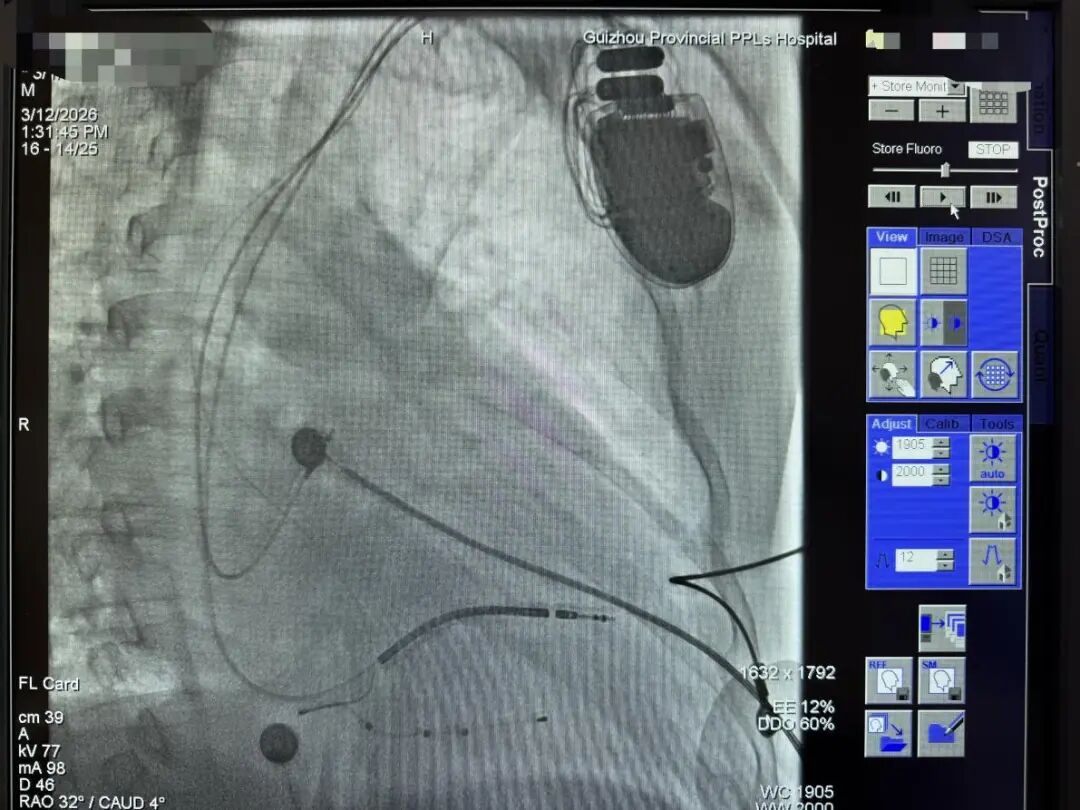

结果:手术顺利完成,术后即刻心电图与影像验证参数良好,术前QRS 160ms,术后VVT起搏模式融合自身心律QRS 120ms,患者术后生命体征平稳参数稳定。

图5 术后影像